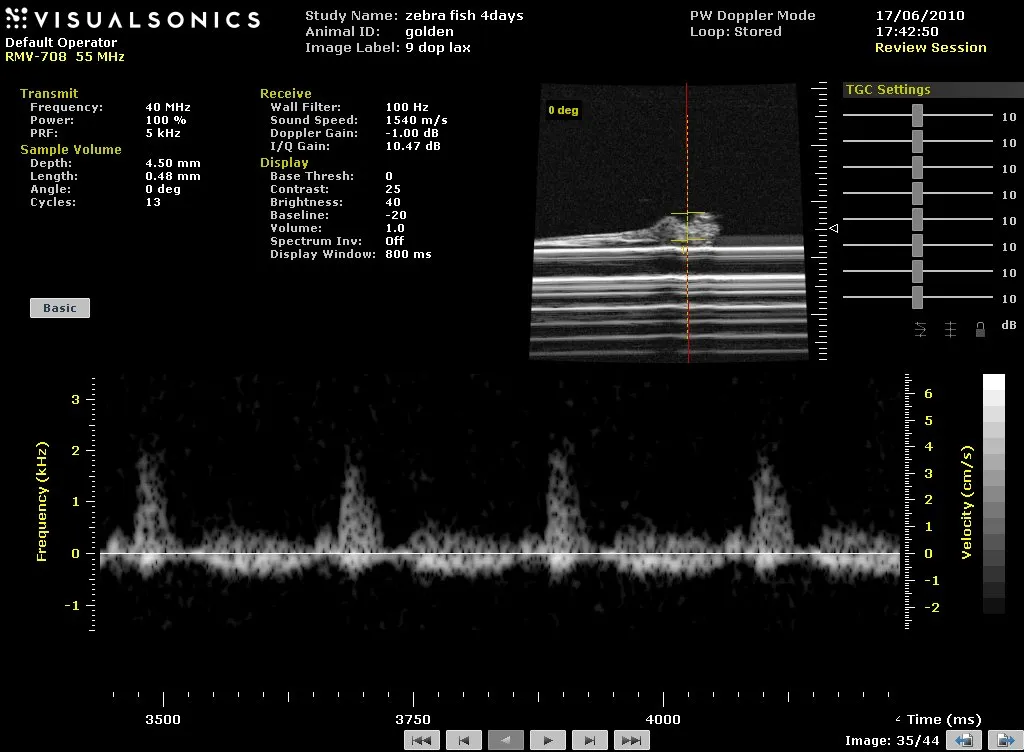

Zebrafish

ultrasound image of 4-day old fish heart

Spectral Doppler trace from a 4day post-fertilisation zebrafish embryo embedded in agar